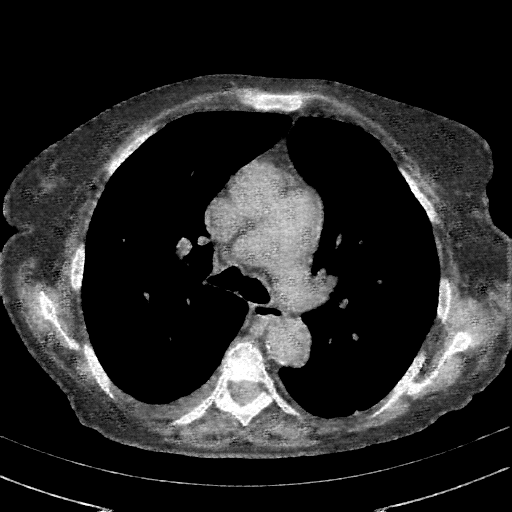

Reconstructed NATIVE CT scan (cycle consistency)

Full window (WL 1023.5, WW 4095 β†’ Low βˆ’1024, High +3071)

Lung window (WL -600, WW 1500 β†’ Low βˆ’1350, High +150)

Mediastinum window (WL 40, WW 400 β†’ Low βˆ’160, High +240)